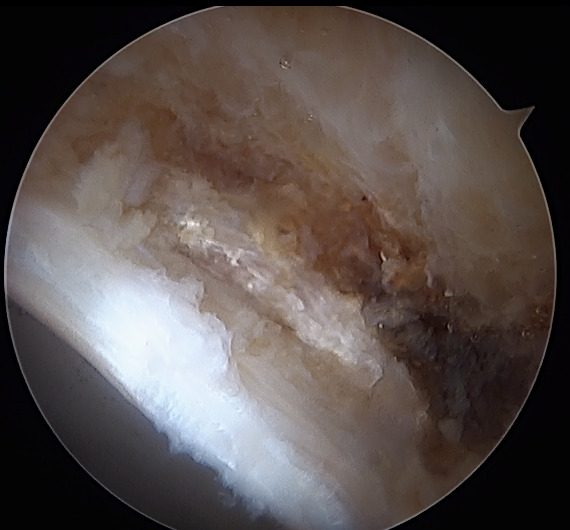

CAM resection

Capsule

- distal capsule suspension sutures / parachute technique

- T capsulotomy - better for large Cam lesions, needs repair

Placing distal capsule sutures to allow parachute technique / distal capsule suspension to expose Cam

T capsulotomy to expose large Cam at head neck junction

Leg position

Anterior Cam

- hip flexed to 45 degrees

- image intensifer rotated 20 degrees posterior and 20 degrees distal to allow Dunn view

Anterior cam resection with hip flexed

Intra-operative Cam resection using Dunn view

Lateral Cam

- hip in extension / internal rotation

Lateral cam resection with hip in extension